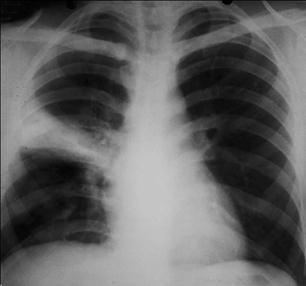

Плевральный выпот осложняет течение ВП в 10-25% случаев и не имеет особого значения в предсказании этиологии заболевания (рис.1-3).

Рис.1-3. Внебольничная пневмония, осложненная экссудативным плевритом.